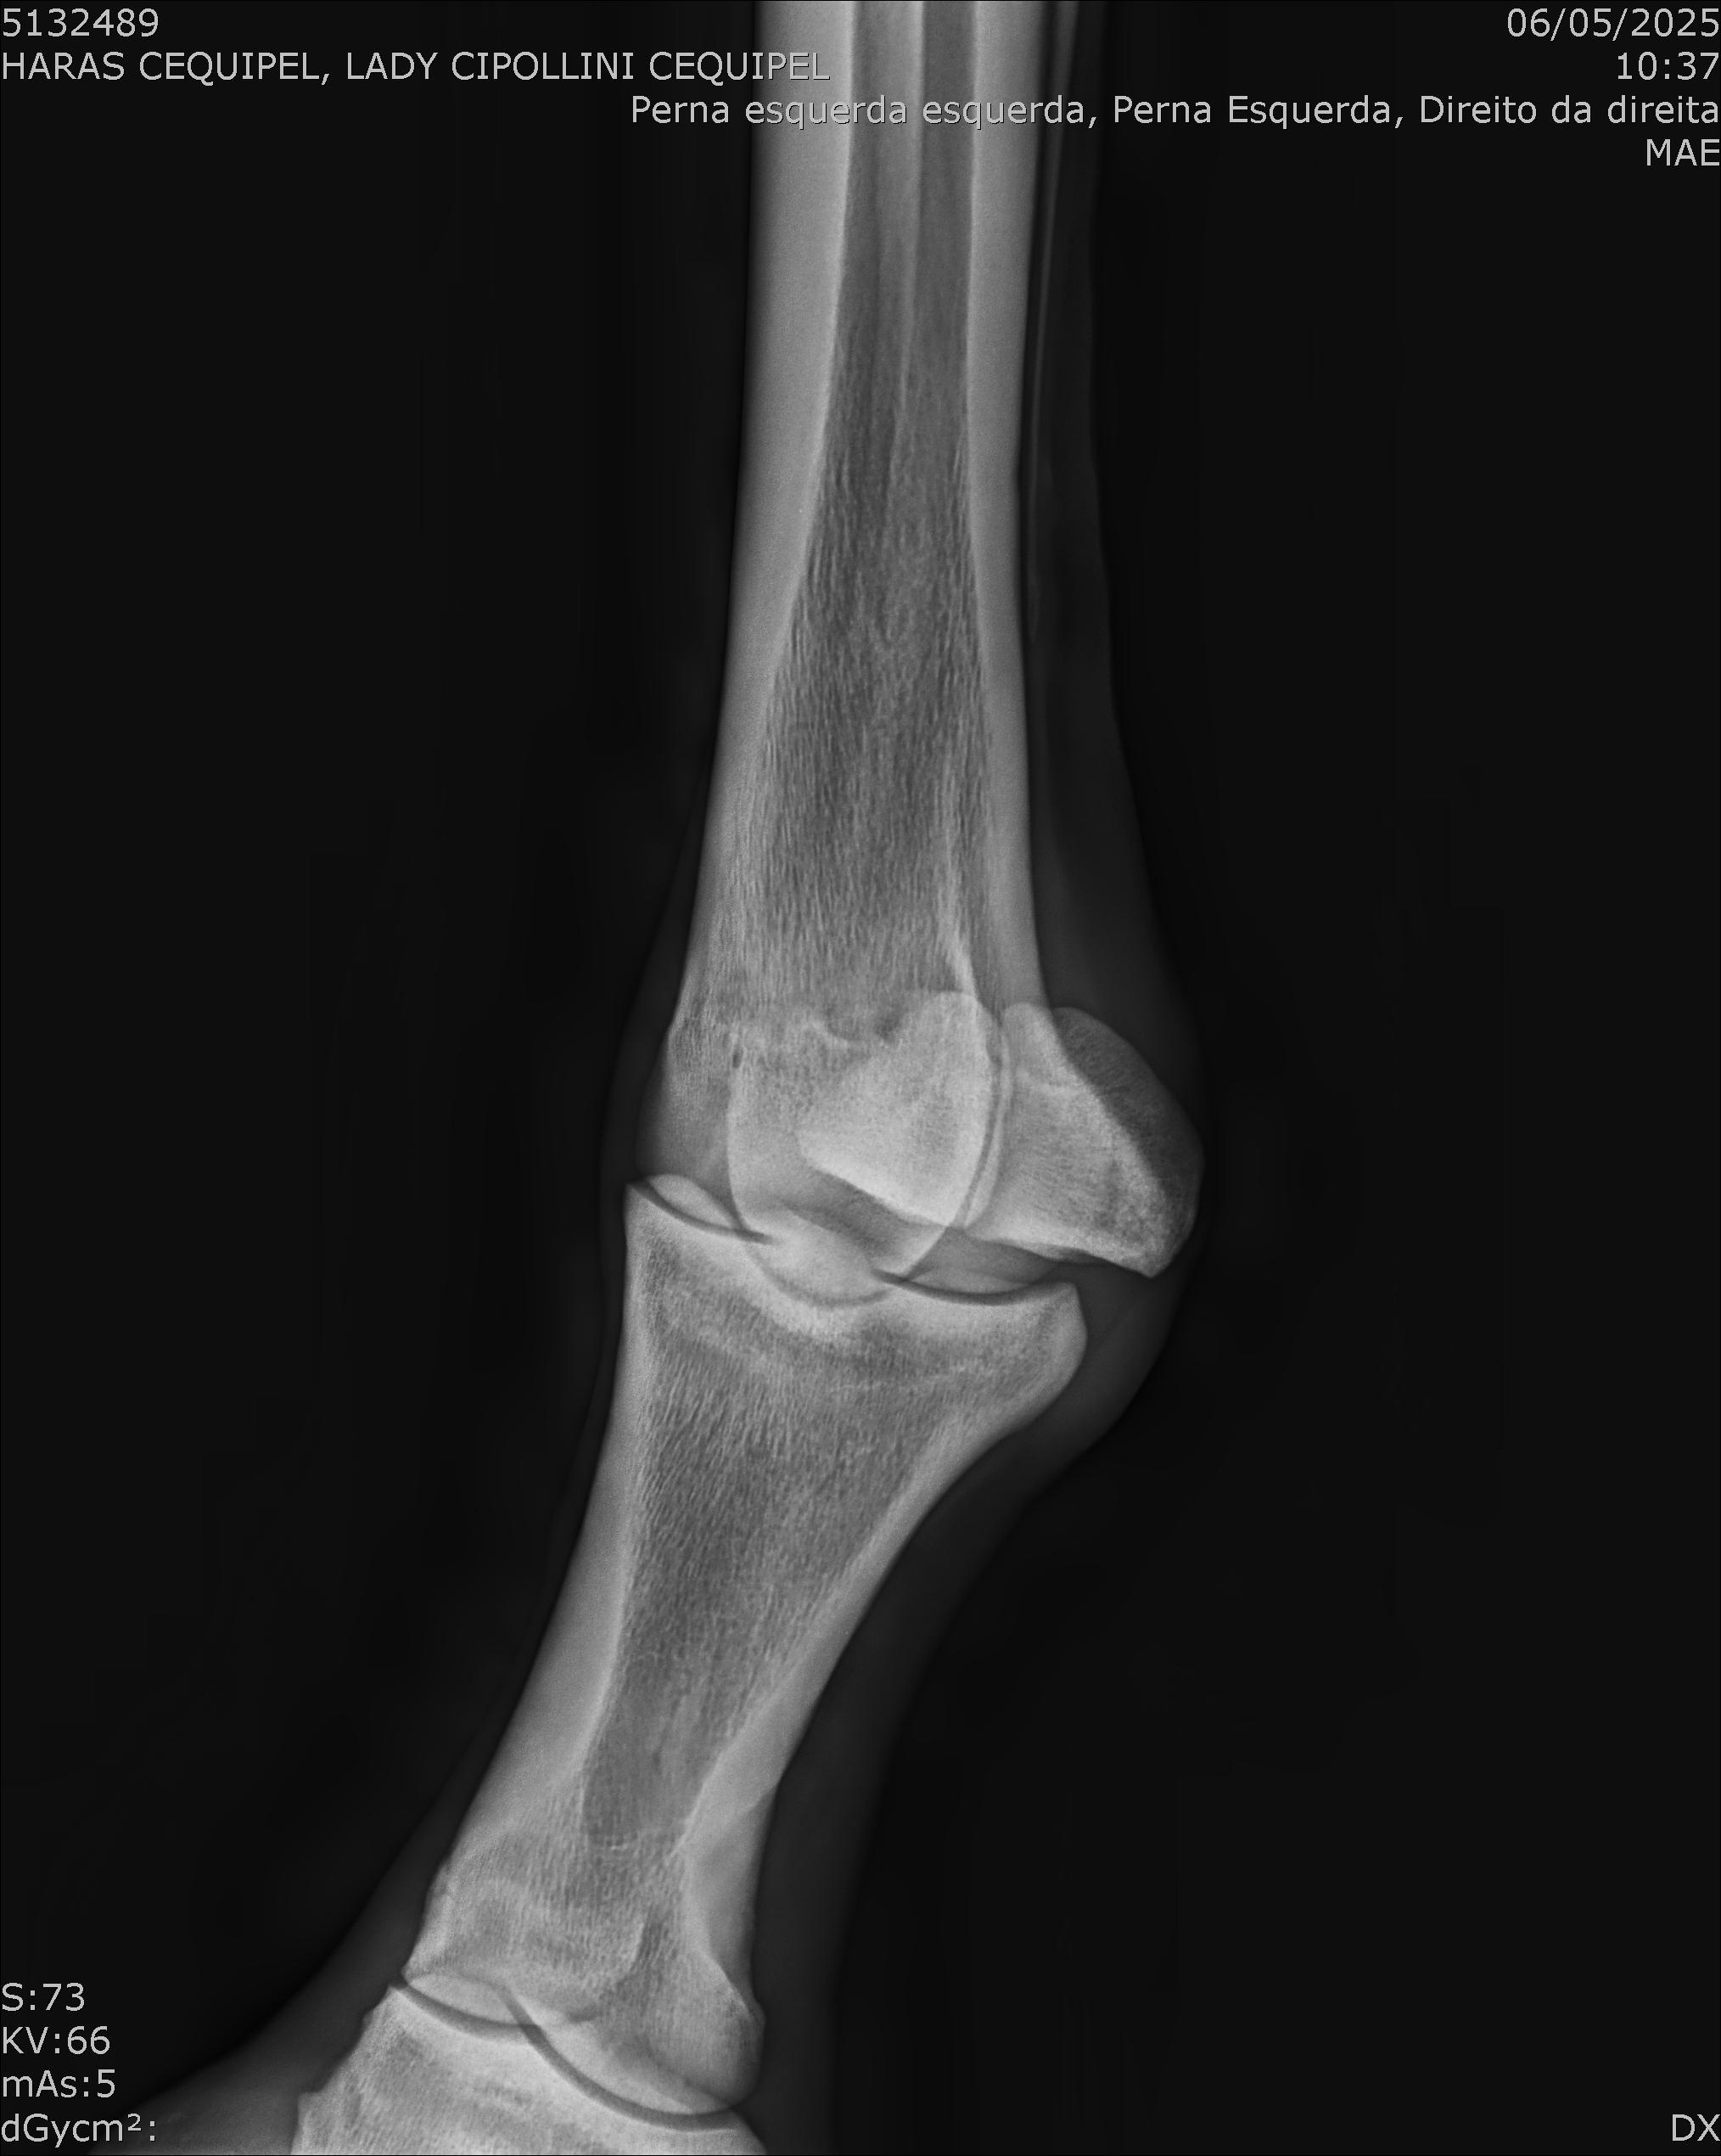

:: RAIOS-X DO LOTE